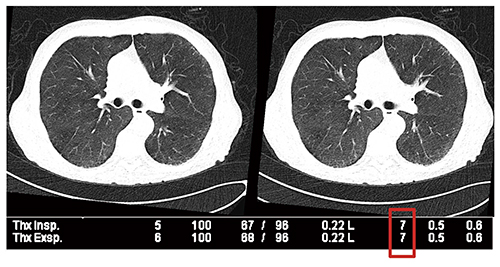

さらに,われわれは腫瘍科の患者に対するルーチン検査に本プロトコルを応用し,air trappingや閉塞性細気管支炎の鑑別に役立てている(図8)。非定型肺炎と移植片対宿主拒絶反応との鑑別の精度向上にも有用である。

図8 超低線量胸部CTによる閉塞性細気管支炎の鑑別診断

(100kV with tin filter →0.098mSv/scan)